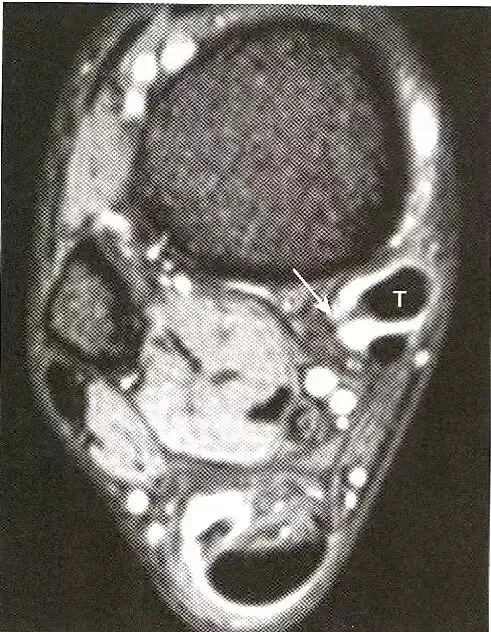

痛风影响肌腱:  肌腱周围分页状的等信号痛风结节